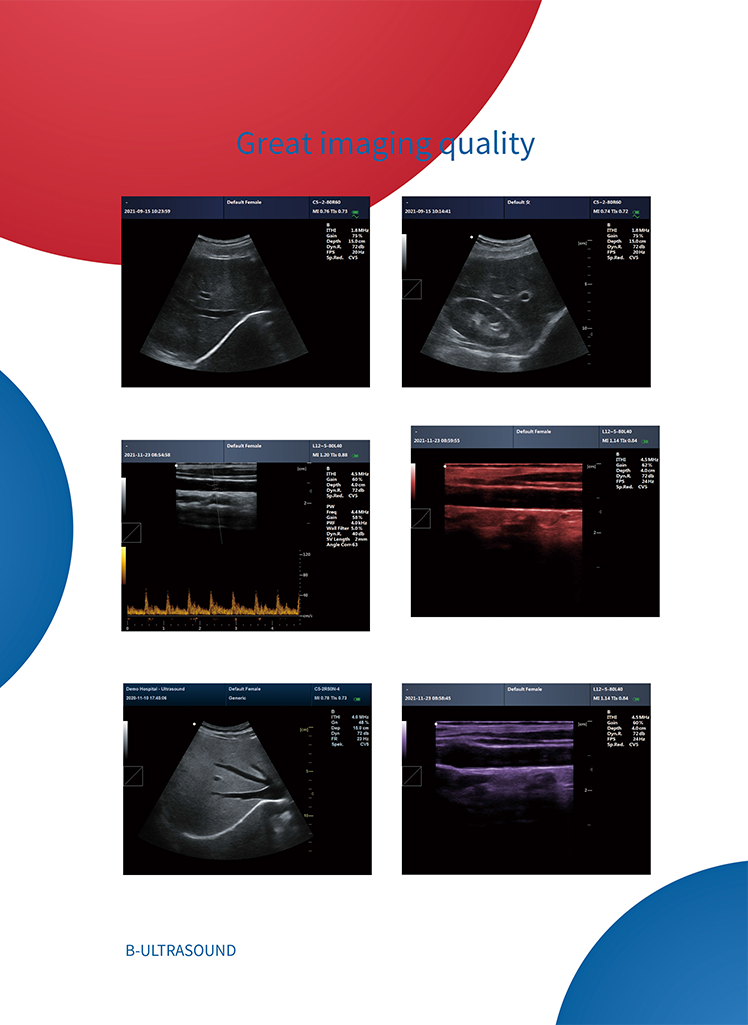

CMS600P2PLUS is a B-Ultrasound Diagnostic System with high resolution and PW Doppler. The system is mainly suitable for the ultrasonic examination of abdomen, obstetrics and gynecology, small organs, urology, etc. It adopts advanced image processing technology (such as digital beam forming technology, tissue harmonic imaging (THI), image speckle suppression, etc.) and digital integrated graphic management system, and the internal professional measurement software package can fully meet the clinic diagnostic requirement.

Pulse wave Doppler (PW)

Working mode: B, 2B, 4B, B/M, M, PW

CONTEC CMS600P2 PLUS portable ultrasound machine pseudo color doppler medical ultrasound Pulse Spectral Doppler instru Images |